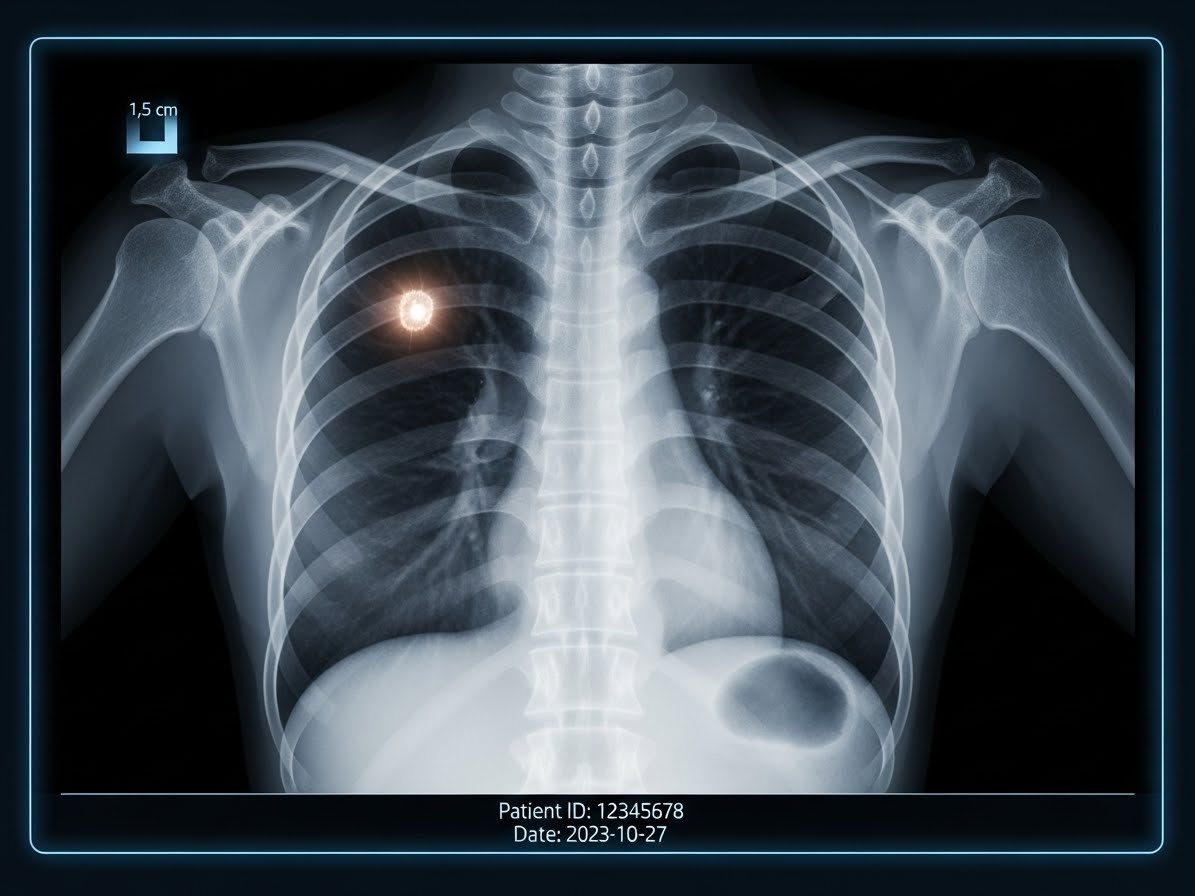

폐결절은 폐에 생기는 3cm 미만의 작은 덩어리를 의미합니다. 흉부 CT 검진의 보편화로 인해 과거보다 훨씬 더 많은 사람이 폐결절을 진단받고 있습니다. 대부분의 폐결절은 양성이며 큰 문제가 되지 않지만, '혹시 암은 아닐까?' 하는 막연한 불안감은 저 또한 충분히 공감하는 부분입니다. 이런 불안감은 정확한 정보 부족에서 비롯되는 경우가 많아요.

2026년 현재, 폐결절 진단 기술은 놀랍도록 발전했습니다. 저선량 흉부 CT는 폐암 조기 발견의 핵심 도구로 자리 잡았으며, 인공지능(AI) 기반의 영상 분석 시스템은 미세한 결절의 특성을 더욱 정교하게 파악하는 데 도움을 줍니다. 이러한 기술 덕분에 우리는 결절의 악성 가능성을 조기에 평가하고, 불필요한 침습적 검사를 줄일 수 있게 되었어요.

특히, 플라이쉬너 학회(Fleischner Society)의 2026년 업데이트된 가이드라인은 폐결절의 크기, 모양, 위치, 환자의 위험 인자 등을 종합적으로 고려하여 맞춤형 추적 관찰 계획을 제시합니다. 이는 의료진이 환자 개개인에게 가장 적합한 관리 방안을 제공하는 데 중요한 기준이 됩니다.